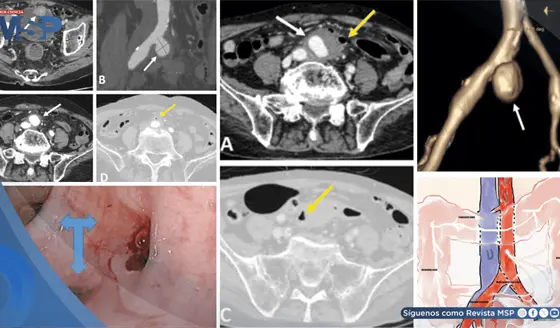

Náuseas y sudoración súbita durante radioterapia resultó en compresión idiopática de vena cava inferior